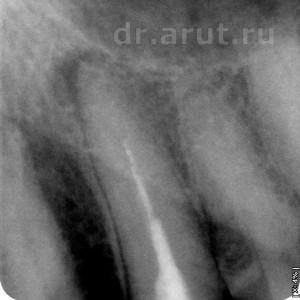

Лечение: После удаления пломбы был обнаружен титановый штифт, который после продолжительных усилий был извлечён, и благодаря этому создан доступ к корневому каналу. Во время распломбирования корневого канала по ходу пломбировочного материала (так как он является ориентиром), оказалось что канал далее непроходим. Проведя Rg-графию 23 зуба вместе с эндодонтическим инструментов выяснили, что в корне 23 зуба создан ложный канал и дальнейшая попытка его прохождения приведёт к перфорации корня. Около верхушки эндодонтического инструмента всё ещё оставалось небольшое количество пломбировочного материала, и было принято решение не продолжать распломбировывать и соответственно оставить его в ложном канале.

Спустя 5 лет сложно уже сказать когда был создан ложный канал — во время последнего лечения, т.е. 5 лет назад, или предпоследнего лечения. Возможно что его не 2 раза лечили, а лечили большее число раз. Сейчас уже это не важно, главное суметь его распломбировать до верхушки.

Такие зубы необходимо лечить под микроскопом, чтоб найти настоящий канал. Но увы очень мало клиник обладают им, а если есть, то врачи всё равно им пользуются редко, только в крайних случаях. Но жизнь показала, что микроскоп не так и необходим, так как его легко можно заменить тем, что есть почти у любого врача… Конечно сложно догадаться что это такое… Ответ очень прост — это современный смартфон, при условии что его фотоаппарат фотографирует качественно и имеет функция макросъёмки. Проведя изучение канала смартфоном, выяснили местонахождение истинного канала и распломбировали его.

- Истинный и ложный канал в клыке

- Прохождение канала на всю длину